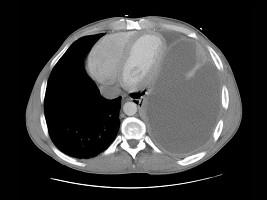

问题 43岁,男,持续高热一周,呼吸急促,胸痛,CT和胸片检查如图,请选出最可能的诊断 ( )

选项 A、肺气肿 B、胸膜间皮瘤 C、肺脓肿 D、气胸 E、脓胸

答案 E